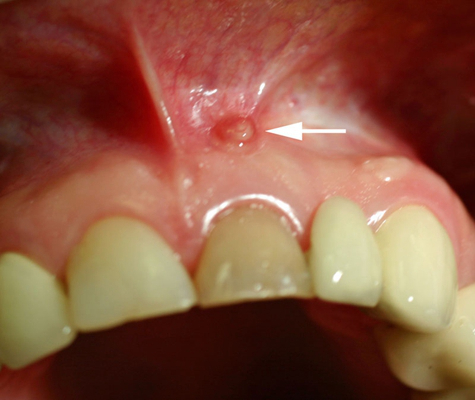

牙齦炎圖片

牙齦炎和牙周炎